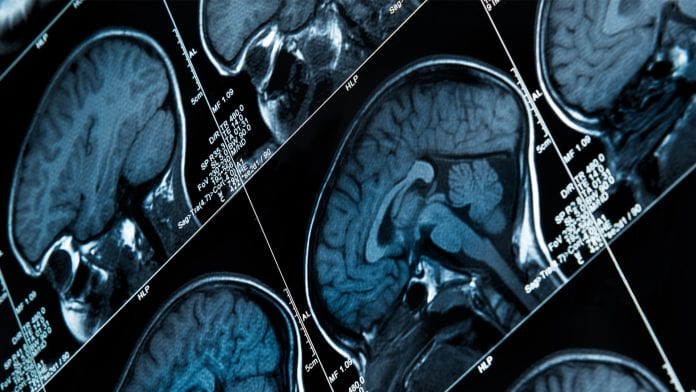

Studies have shown that drug treatment could improve language skill and normalize centrotemporal spikes in electroencephalograph (EEG) tests, therefore it is important to distinguish epilepsy patients from healthy individuals. While studies have found that magnetic resonance imaging (MRI) and functional magnetic resonance imaging (fMRI) are promising for differentiating BECT patients from healthy individuals, these imaging techniques are mainly based on the doctor’s knowledge and diagnostic ability, and therefore is subject to have limitations, such as low accuracy.

This particular study proposed a novel classification method that unifies the predictions of three different types of brain imaging data: handcrafted features from MRI (51 brain characteristics associated with the disease), MRI and fMRI. The researchers passed the imaging data respectively through three different machine learning methods, including two specially designed deep neural networks, and then combined the outcomes into a final decision-making neural network to determine whether a patient has BECT.